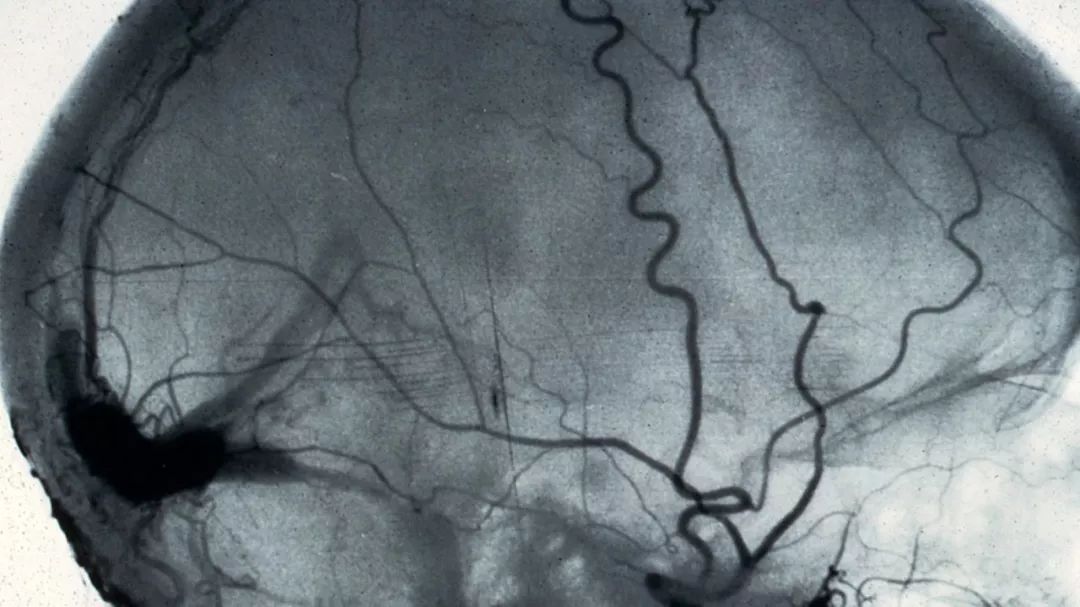

△ 血管造影术(angiogram)拍到的脑部血管。 血管造影术是利用X光观察血管堵塞的医学方法。